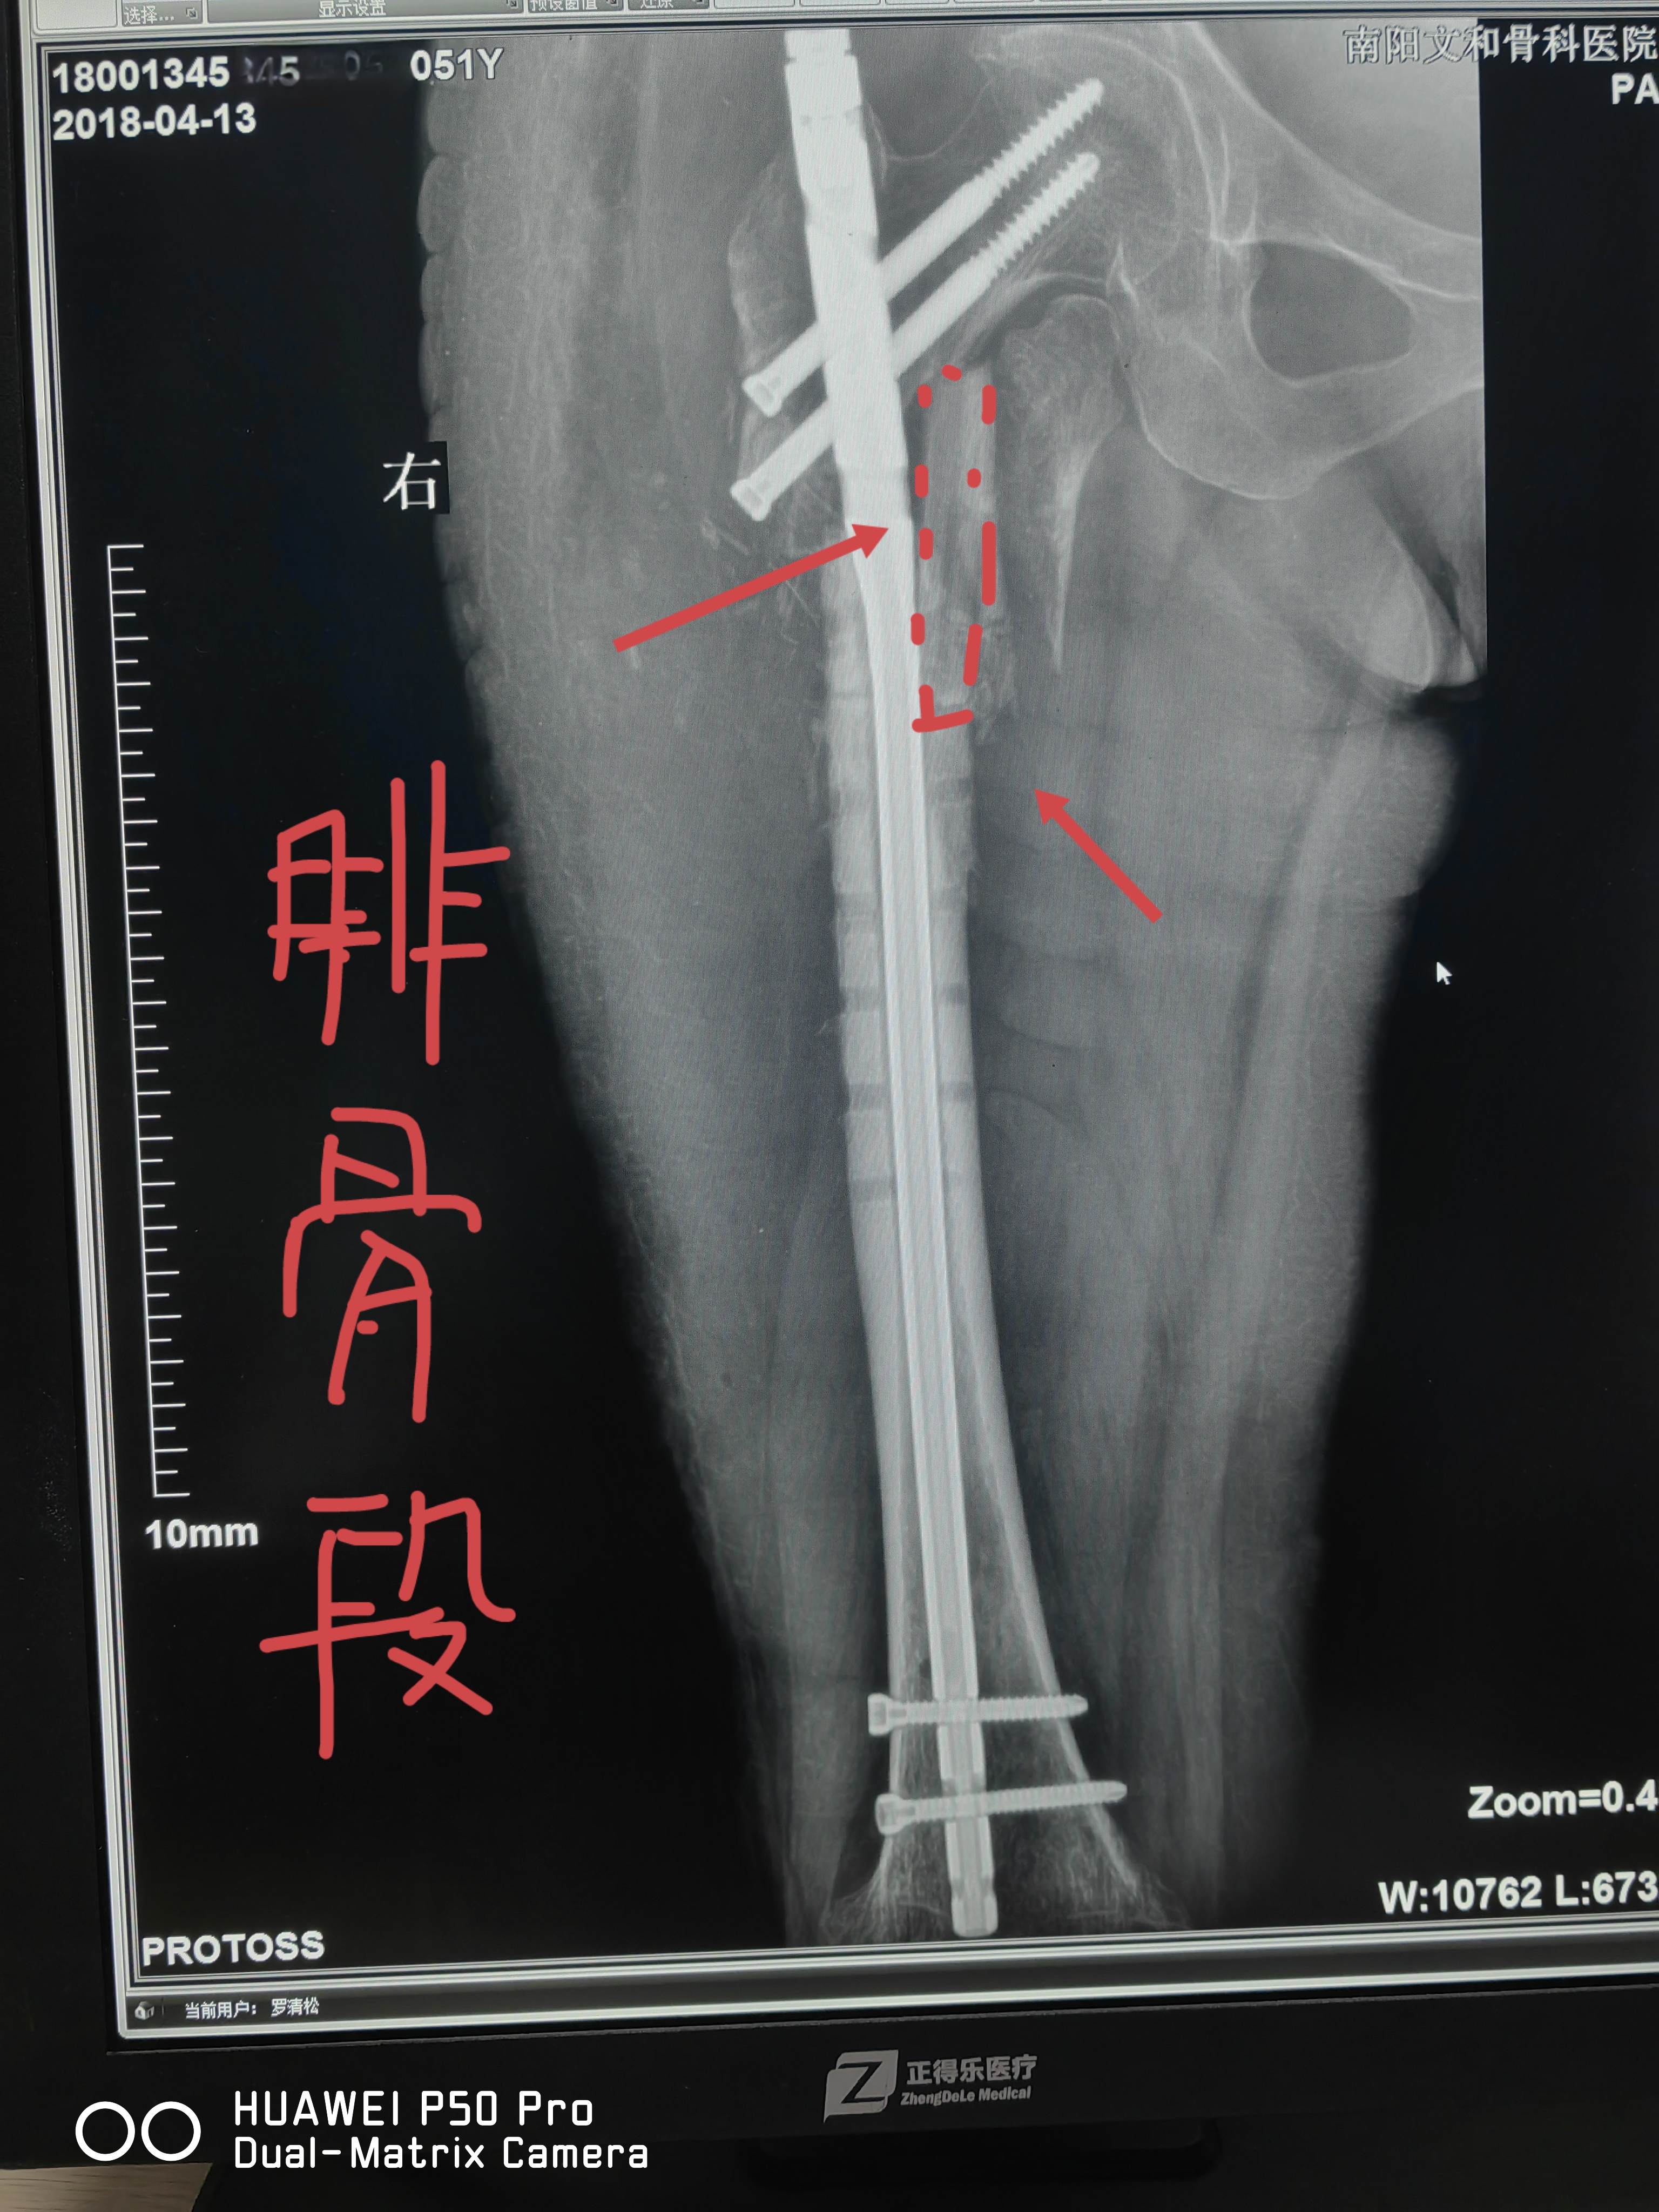

股骨近端骨折骨不连+钢板断裂,重建髓内钉翻修+游离腓骨段支撑

简要病史:2017年7月因右股骨近端骨折在当地医院行手术治疗,后骨折不愈合,于当地医院再次行植骨术。2018年3月15出现右大腿畸形,疼痛,拍片示钢板断裂,骨折不愈合,当地医院牵引2周后,于2018年3月29日来我院治疗。

术前诊断:右股骨骨折术后骨不连伴内固定断裂。

术前讨论结果:内固定取出,髓内钉固定,游离骨瓣内侧支撑植骨术。

于2018.04.08行手术。

内侧缺乏支撑

取腓骨段支撑